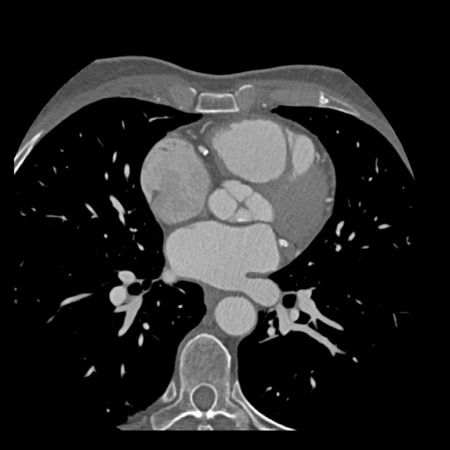

case 1 – CAD-RADS 2/P1

First, scroll through the scan.

Not all images are included. Some images without any abnormalities are skipped

from the series.

How would you describe the findings on the coronary CTA?

The findings are:

- Agatston score of

this patient was 14 (P1). Please, also note the calcification of the aortic valve. - Some partially

calcified and calcified plaques are present in the LAD with mild stenosis

(25-49%). - Calcified-plaque in

the LCX causing minimal stenosis (<25%). - Non-calcified

plaque in the distal RCA causing minimal stenosis (<25%). - This patient classifies

as CAD-RADS 2/P1, which means no further workup is needed.